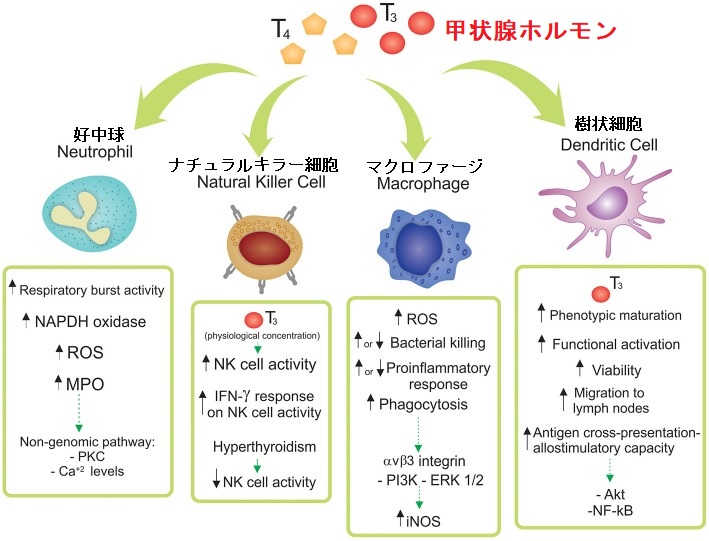

甲状腺機能低下症と免疫力低下には、いろいろな意見があります。甲状腺ホルモンの低下そのものが、免疫系統に直接影響する証拠はありません。[ただし、最近の基礎医学研究では甲状腺ホルモンそのものが免疫細胞に直接影響する結果が大半を占めています(下記)]

基礎医学の分野では、「甲状腺ホルモンそのものが免疫系の細胞に作用し活性化させる」研究結果が大半を占め、感染防御に大きな役割を担うとされます。(甲状腺と自然免疫 )

(Front Endocrinol (Lausanne). 2019 Jun 4;10:350.)